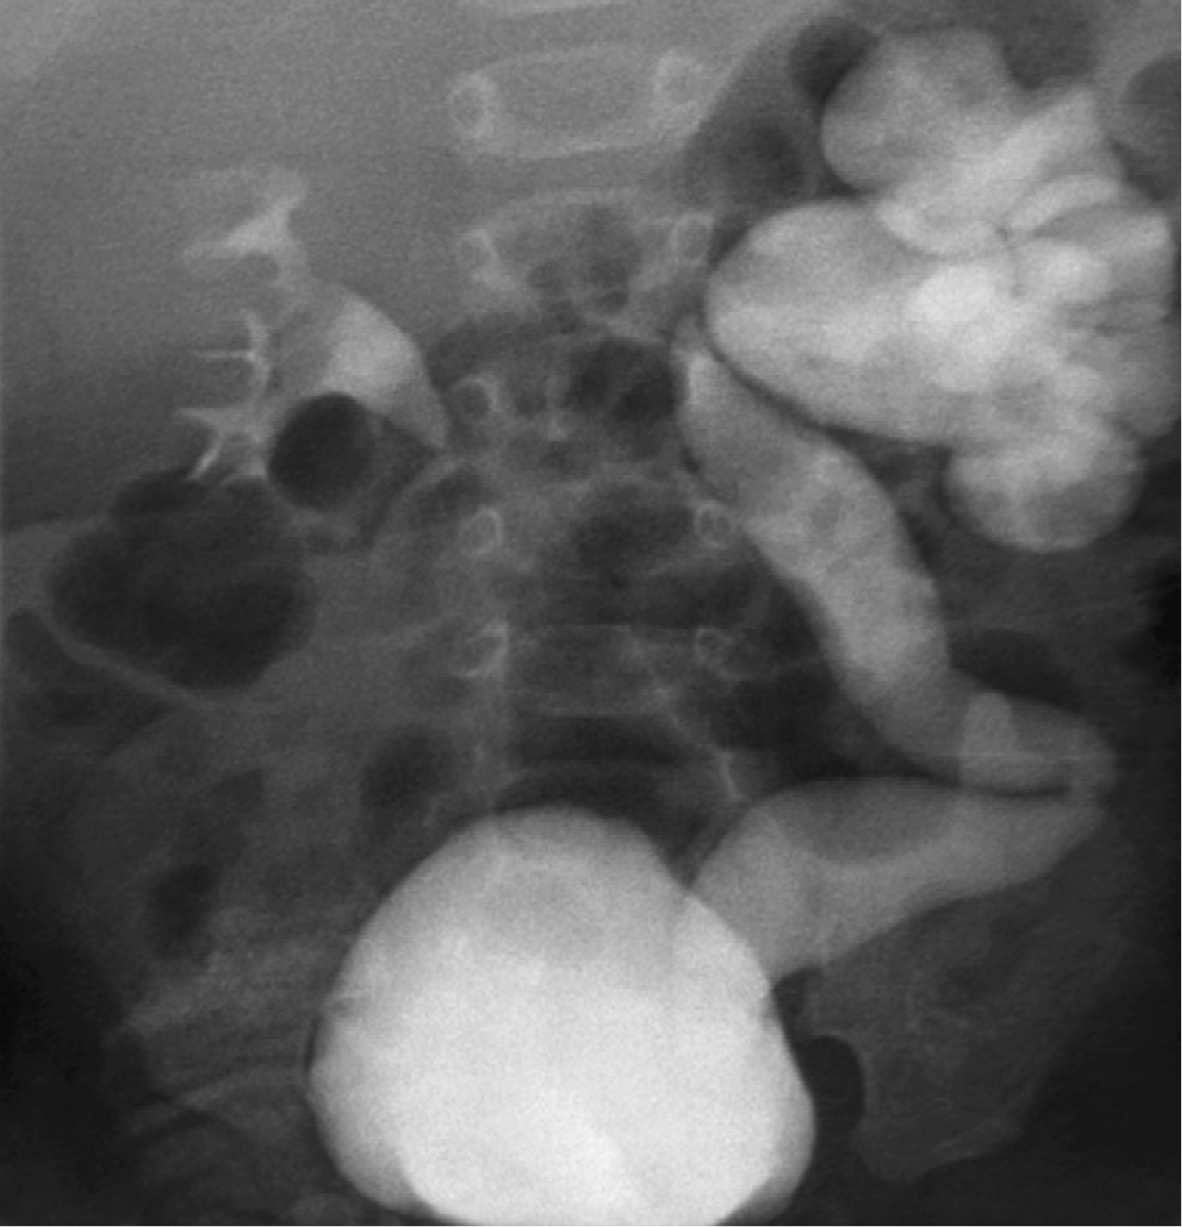

Vesicoureteral Reflux Grading

Most low-grade VUR resolves sponta- neously by the age of 5 to 6 years unless there is an underlying anatomic abnormality.

Figure example:

Right side - Grade 2

Left side - Grade 5